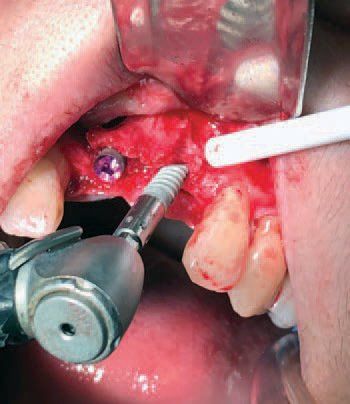

“On the day of the procedure, we anesthetized the patient and opened a large flap in the interior region with horizontal and two vertical releases,” said Dr. Mark. “I located the vertical releases two teeth away from the area where I would operate to allow for a tension-free flap post surgery. The failing implant could be clearly seen touching the surface of the bone (Figure: C) which was then removed without incident.